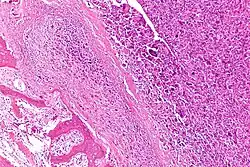

| Intermediate-magnification micrograph of an osteosarcoma (center and right of image) adjacent to non-malignant bone (left-bottom of image): The top-right of the image has poorly differentiated tumor. Osteoid with a high density of malignant cells is seen between the non-malignant bone and poorly differentiated tumor (H&E stain). | |

Microscopically: The characteristic feature of osteosarcoma is presence of osteoid (bone formation) within the tumor. Tumor cells are very pleomorphic (anaplastic), some are giant, numerous atypical mitoses. These cells produce osteoid describing irregular trabeculae (amorphous, eosinophilic/pink) with or without central calcification (hematoxylinophilic/blue, granular)—tumor bone. Tumor cells are included in the osteoid matrix. Depending on the features of the tumor cells present (whether they resemble bone cells, cartilage cells, or fibroblast cells), the tumor can be subclassified. Osteosarcomas may exhibit multinucleated osteoclast-like giant cells.[22]